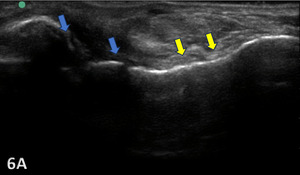

COMPLETE TEAR OF CFL

Figure 6A: Complete tears might show anechoic defects (blue arrows) of the CFL along with a hypoechoic and wavy appearance (yellow arrows) of the torn ligament.